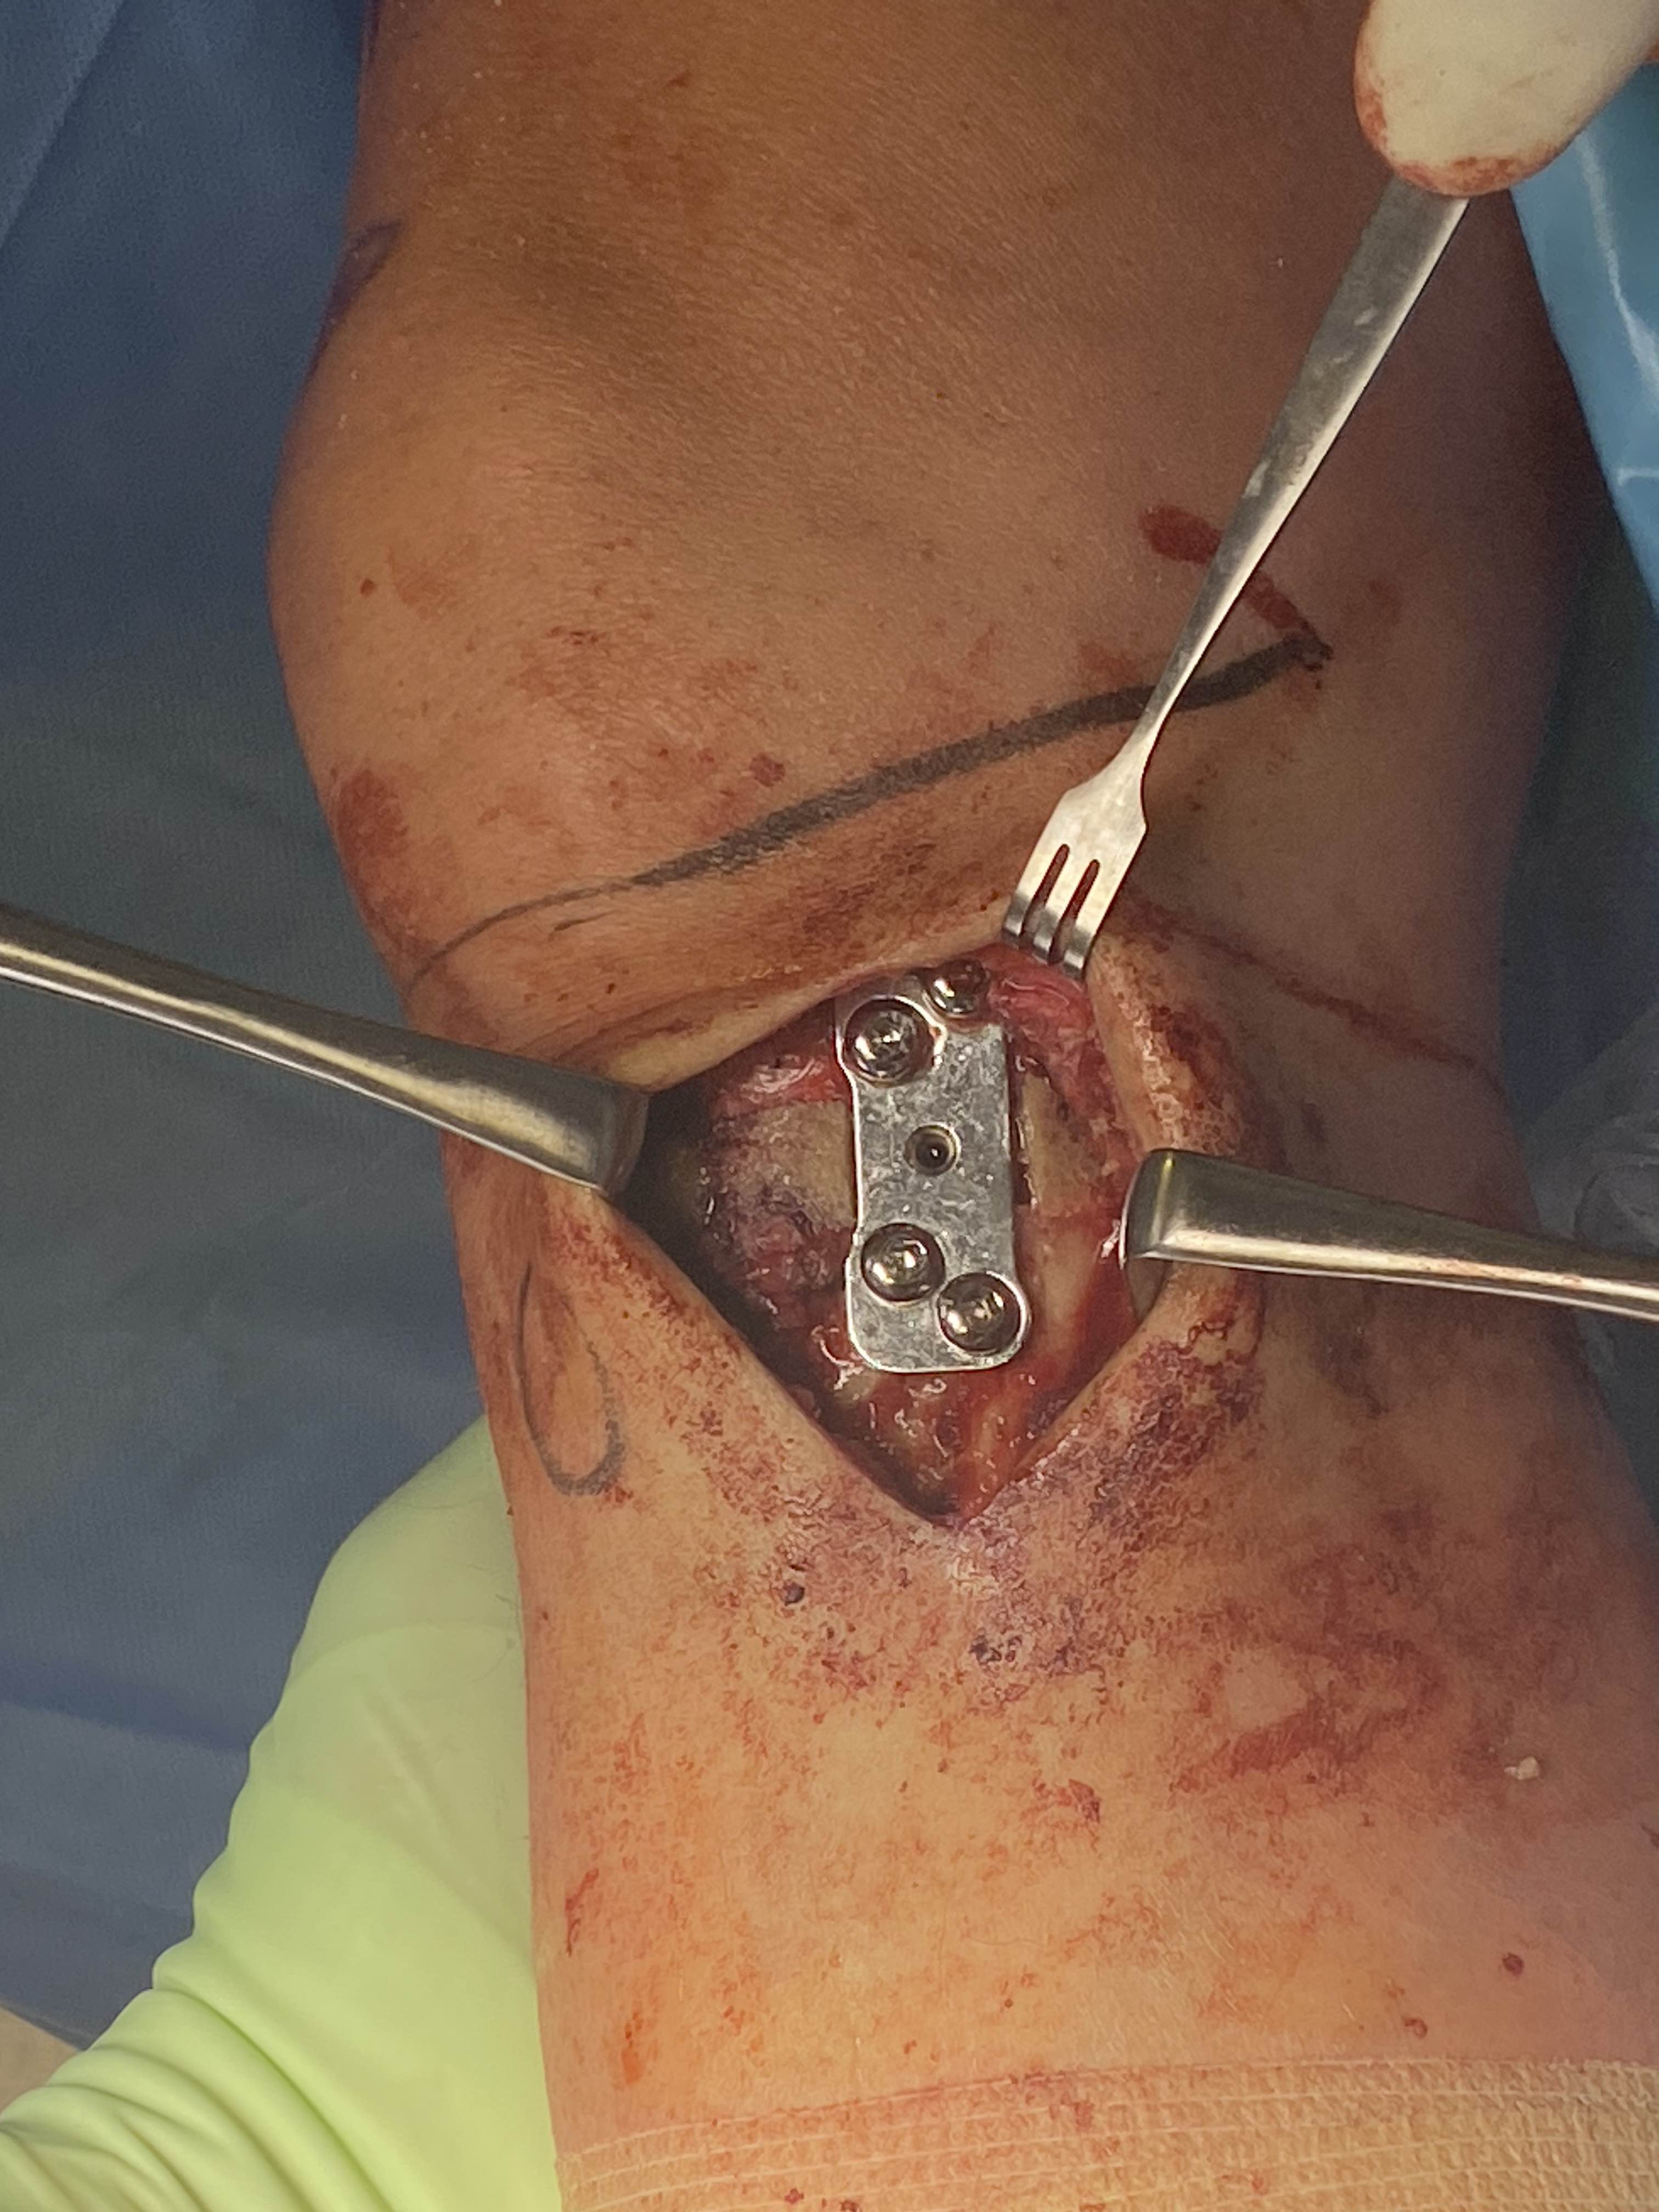

Approach

- medial incision close to midline to incorporate into later TKA

- between tibial tuberosity and MCL

- L shaped incision of sartorius fascia

- identify and elevate pes anserinus, as may have to slide plate under

- identify and elevate MCL posteriorly

Exposure

- must expose and protect entire posterior tibia subperiosteally

- should be able to place finger entirely across tibia to proximal tibio-fibular joint

- must expose and protect patella tendon above tibial tuberosity

- place Langenbeck / Homan retractors anteriorly and posteriorly

Stabilisation

- locking plates